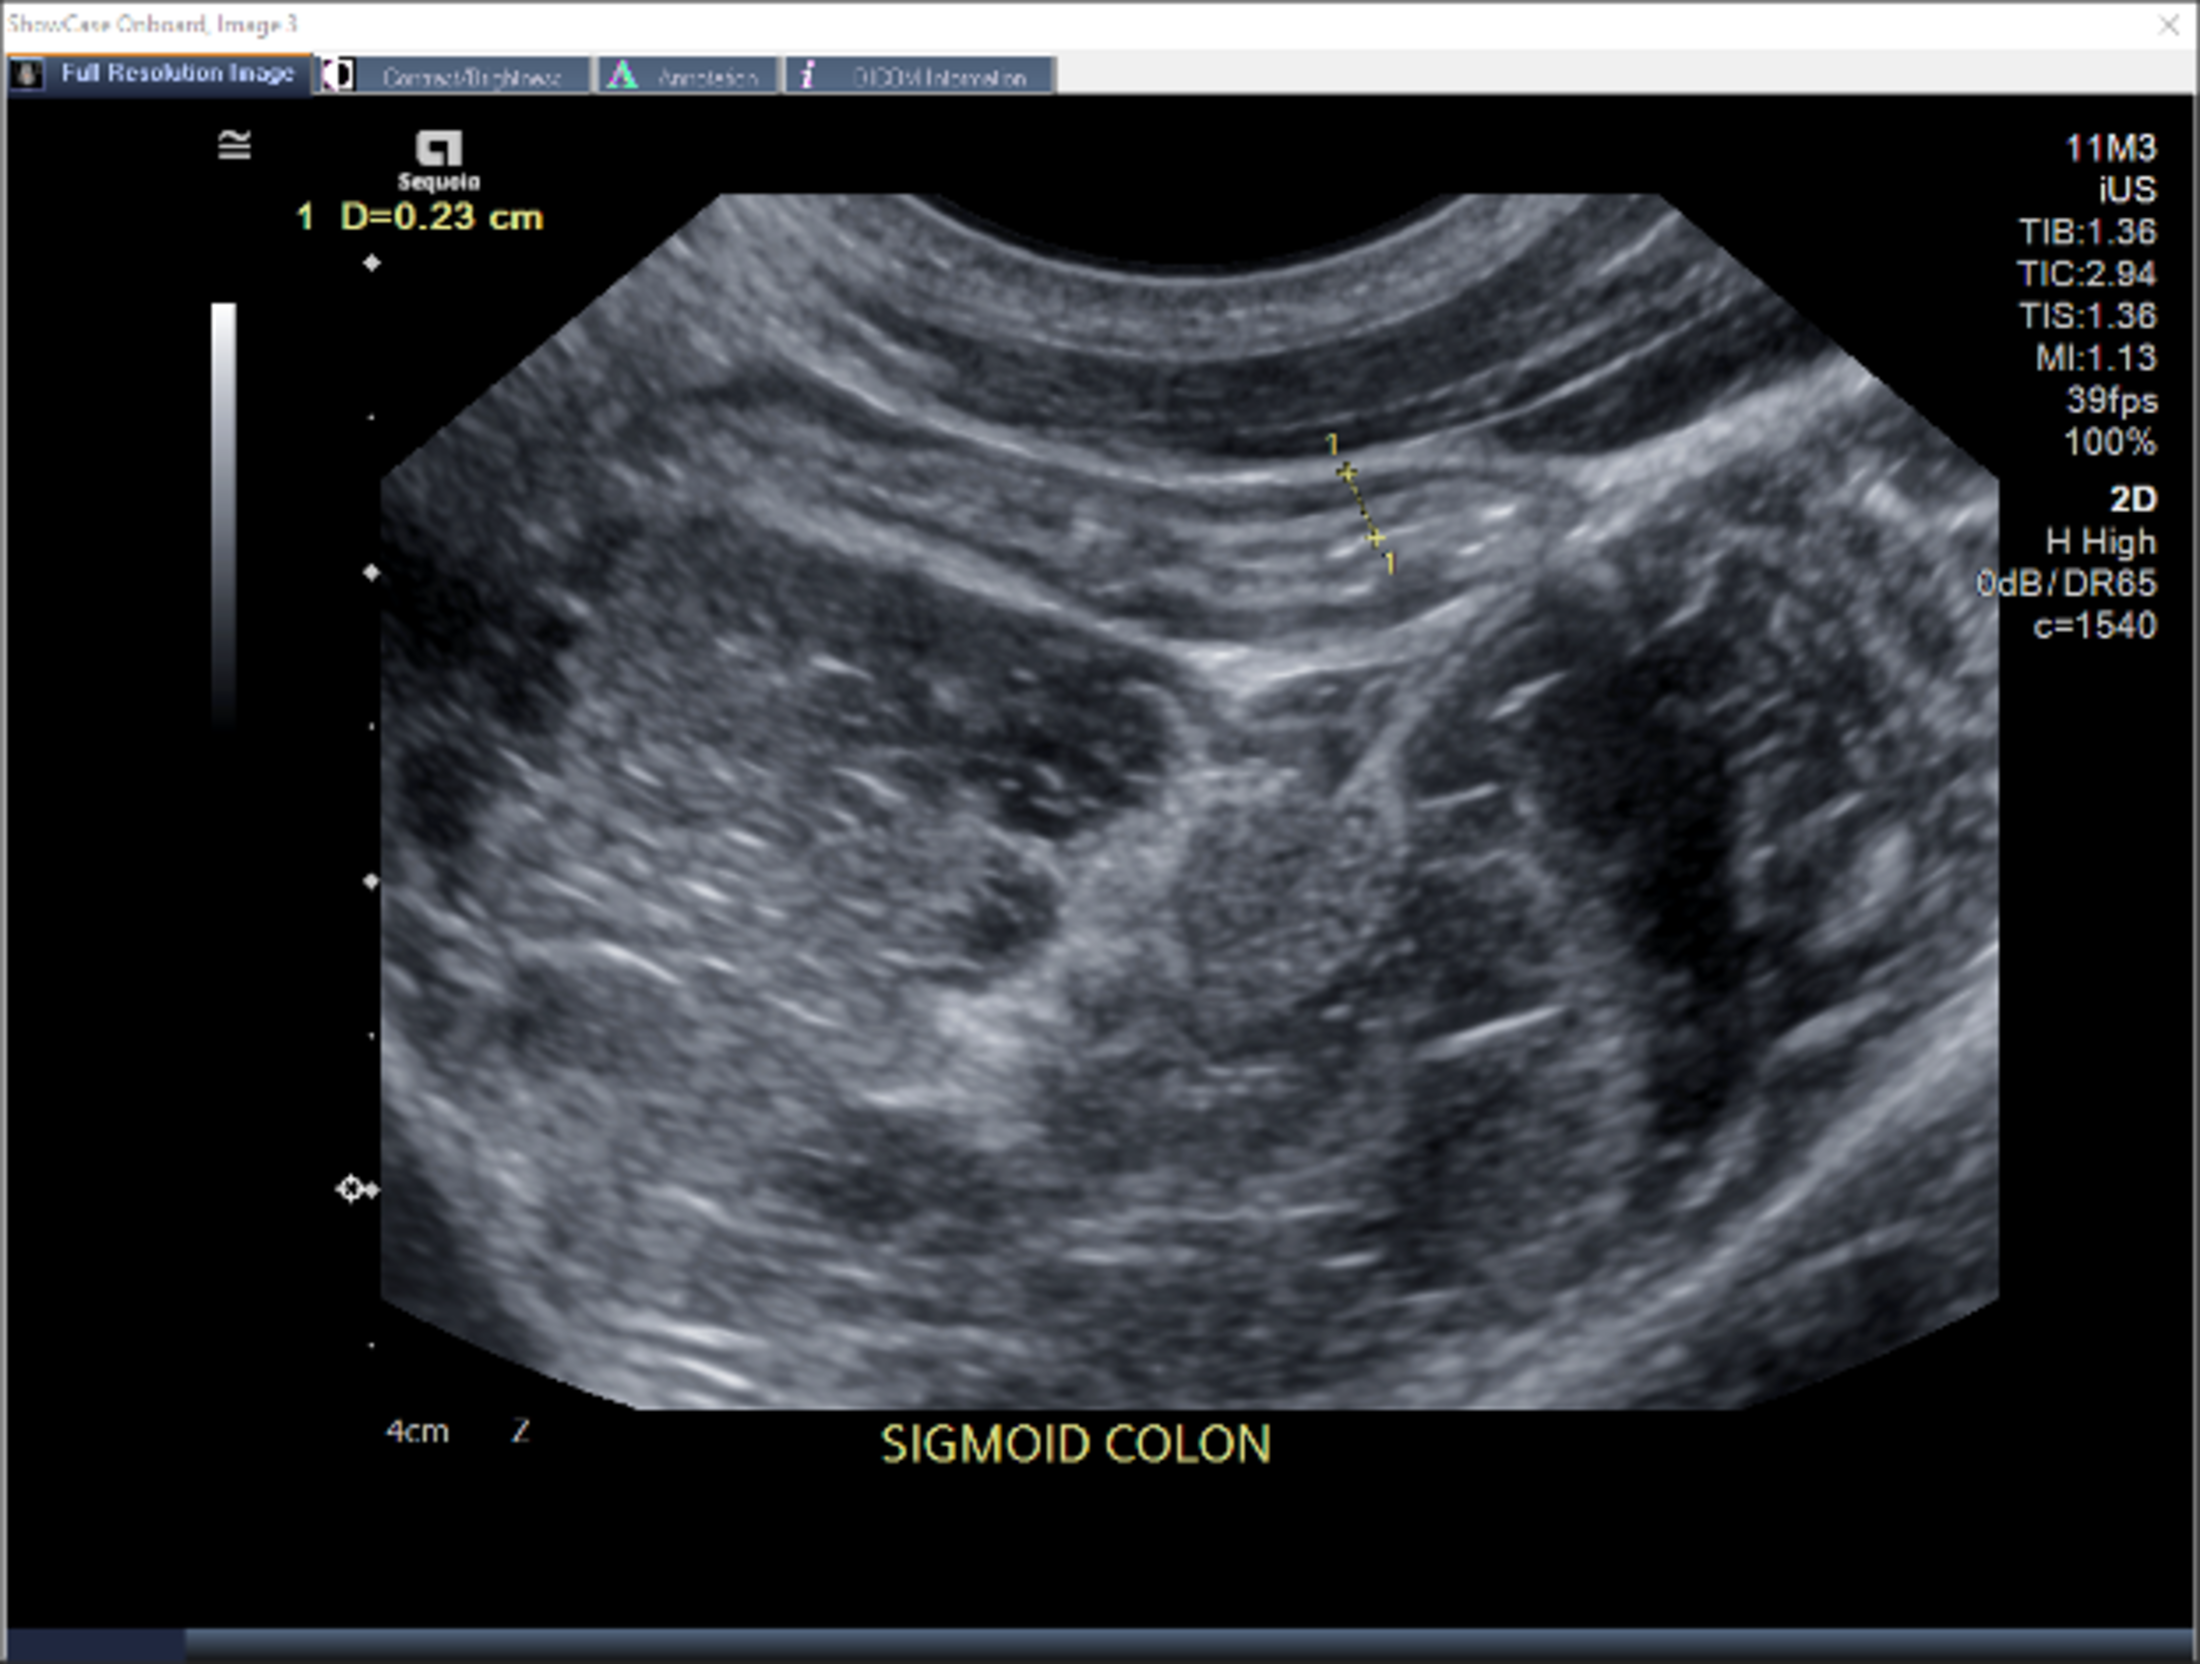

IUS is essentially an abdominal ultrasound that provides highly accurate, high-resolution imaging of the intestine and colon. It does not require any of the more intensive bowel preparation needed for invasive procedures like colonoscopies, and it does not have any side effects like those that might occur from radiation.

IUS allows visibility of both the large intestine (colon) and the small intestine (terminal ileum), and disease activity can be assessed using several markers, such as bowel wall thickness, hyperemia (increased blood flow) and disruption of wall layers.

“With IUS, I’m able to see how thick the bowel wall is and if there is an increased blood flow to that area, which would indicate inflammation,” explains Suppa. “I can also see if there is any disruption to the layers of the bowel wall or signs of complications such as strictures.” This allows him to determine how well a patient is responding to a prescribed treatment without waiting for lab results or the need to schedule other procedures or imaging.